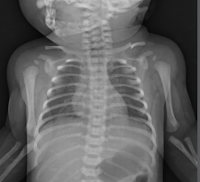

bebeklerde köprücük kemiği kırığı

bebeklerde köprücük kemiği kırığı.

omuz travmasi